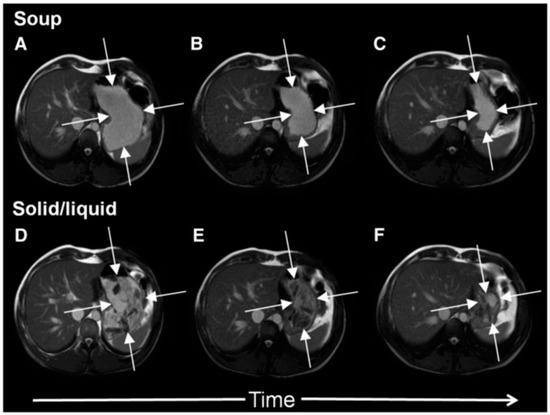

In Figure 2 it is shown how a typical solid meal taken with water drink (D–E) fills the stomach with heterogeneous content from which the fluid can be preferentially emptied causing a faster fall in total gastric volume and hence feeling of fullness. We compared this with the same meal blenderised to create a homogeneous soup (images A–C) and showed that the volume of the stomach fell more slowly with the soup and this was associated with more prolonged satiety [5].

Figure 2. Cross-sectional MRI images showing a stomach at 0, 60 and 120 min after ingesting either roast chicken and vegetables (panels D, E and F respectively) or the same meal blenderised to create a homogeneous soup (panels A, B and C respectively). The solid meal taken with water appears heterogeneous, fluid can be preferentially emptied reducing gastric volume and hence the feeling of fullness. The same meal when blenderised appears homogeneous, gastric volumes fall more slowly with time which is associated with more prolonged satiety. Reproduced from [5], Oxford University Press 2012, with permission.